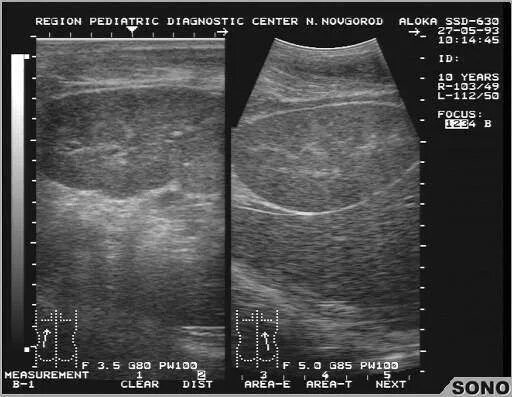

Диффузные изменения структур почечных синусов